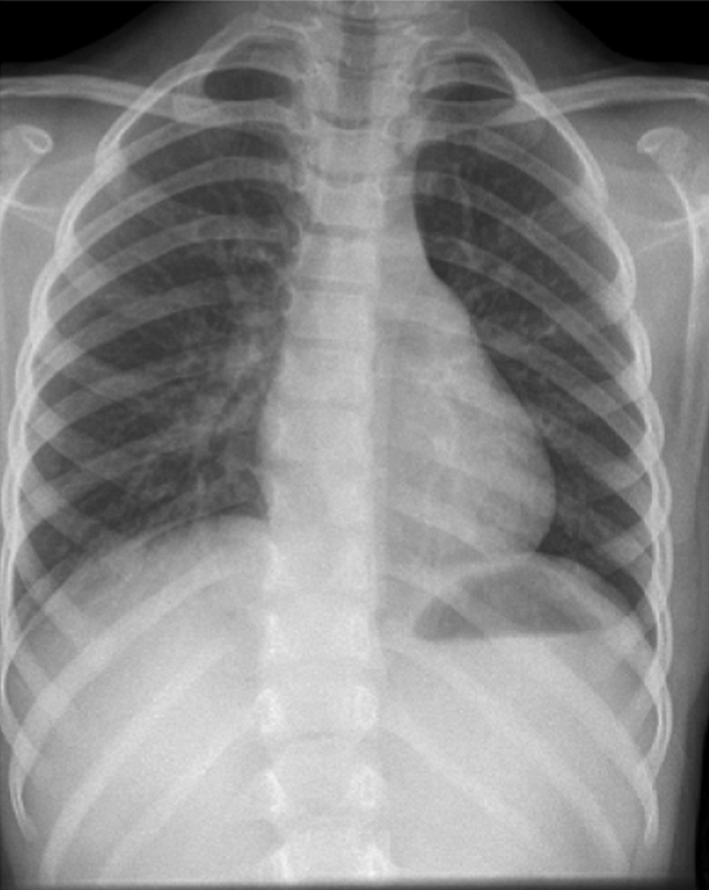

Bony complications include sclerosis, premature epiphyseal fusion, long bone deformity, growth arrest and progressive kyphosis [5, 19]. Spinal involvement has been reported from the mid-cervical spine to the sacrum. This occurs in the form of “migratory spondylitis” or “saltatory spondylitis” [26]. X-ray picture is predominantly of the chronic sclerosing type. Vertebral deformity due to compression and total collapse (vertebra plana) is rare [26]. Spondylodiscitis only develops as secondary destruction following the spondylitis, thus helping in differentiating from the spondyloarthropathies. Spinal cord compression is extremely rare and till date only one case of severe kyphosis, due to CRMO has been reported which needed anterior decompression and fusion [1]. Vertebra plana has been described as a complication of CRMO [32]. Scoliosis is commonly seen in female patients of the adolescent age group. In case of acute painful onset, the possibility of CRMO needs to be kept in mind. Our patient (who had a previous chest X-ray prior to this episode with no evidence of scoliosis; Fig. 1) had a long C-shaped thoracic scoliosis which was convex to the right. The apex of the curve was at T10 and the magnitude of the curve was 22° as measured by the Cobb angle method. We think that the particular pattern of scoliosis was a protective mechanism to offload the right sided T10 vertebral pedicle. Prognosis is generally good, most lesions healing with sclerosis, although the disease can relapse and remit over many years [2, 9, 12, 19] (Figs. 2–8).

Fig. 1.

Old X-ray spine showing no evidence of scoliosis

Fig. 2.

AP thoracic spine showing right convex scoliosis with Cobb’s angle of 22° with apex AT T10